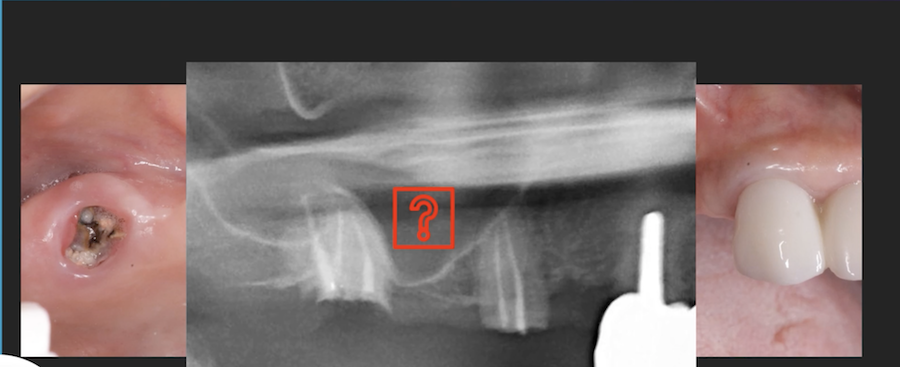

Implants placed too close: Is this restorable?

I am feeling really humble. I’ve placed multiple implants and thinking this should be a straightforward case. I was wrong. I know it’s poorly planned and freehand did not go well. Are these restorable? Should I explant and redo? If I do remove these, how easy is it to remove these?